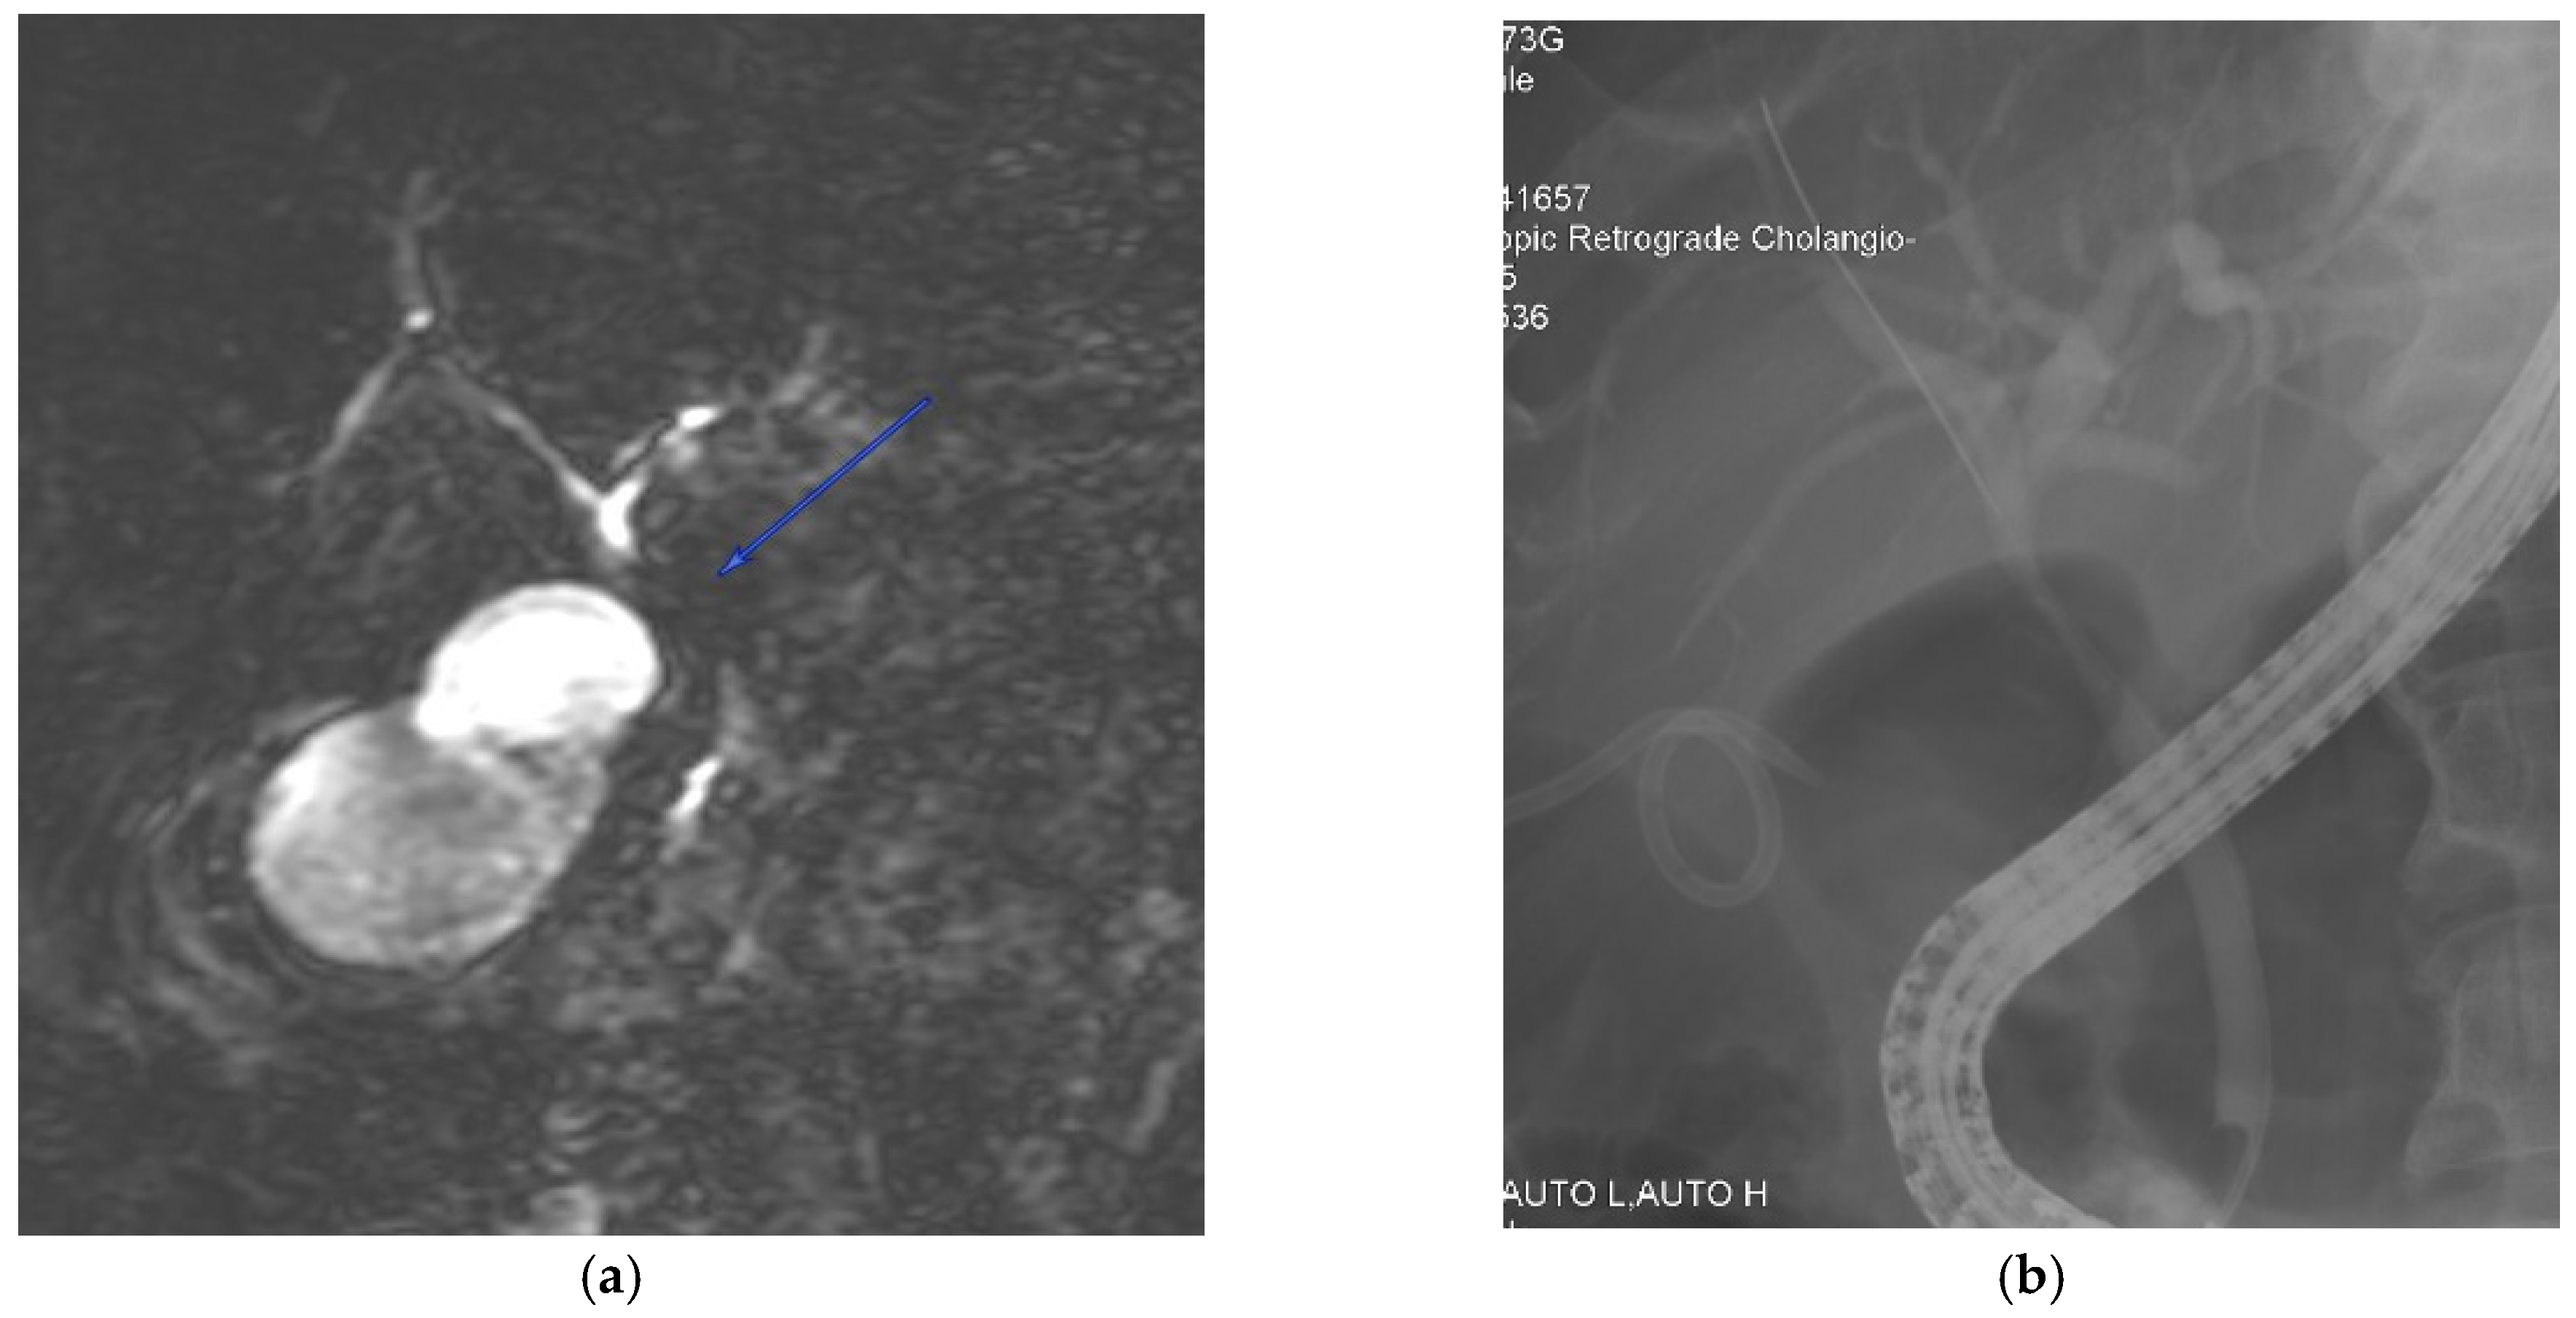

5.3. Magnetic Resonance Cholangiopancreatography (MRCP)

5.4. Endoscopic Retrograde Cholangiopancreatography (ERCP)